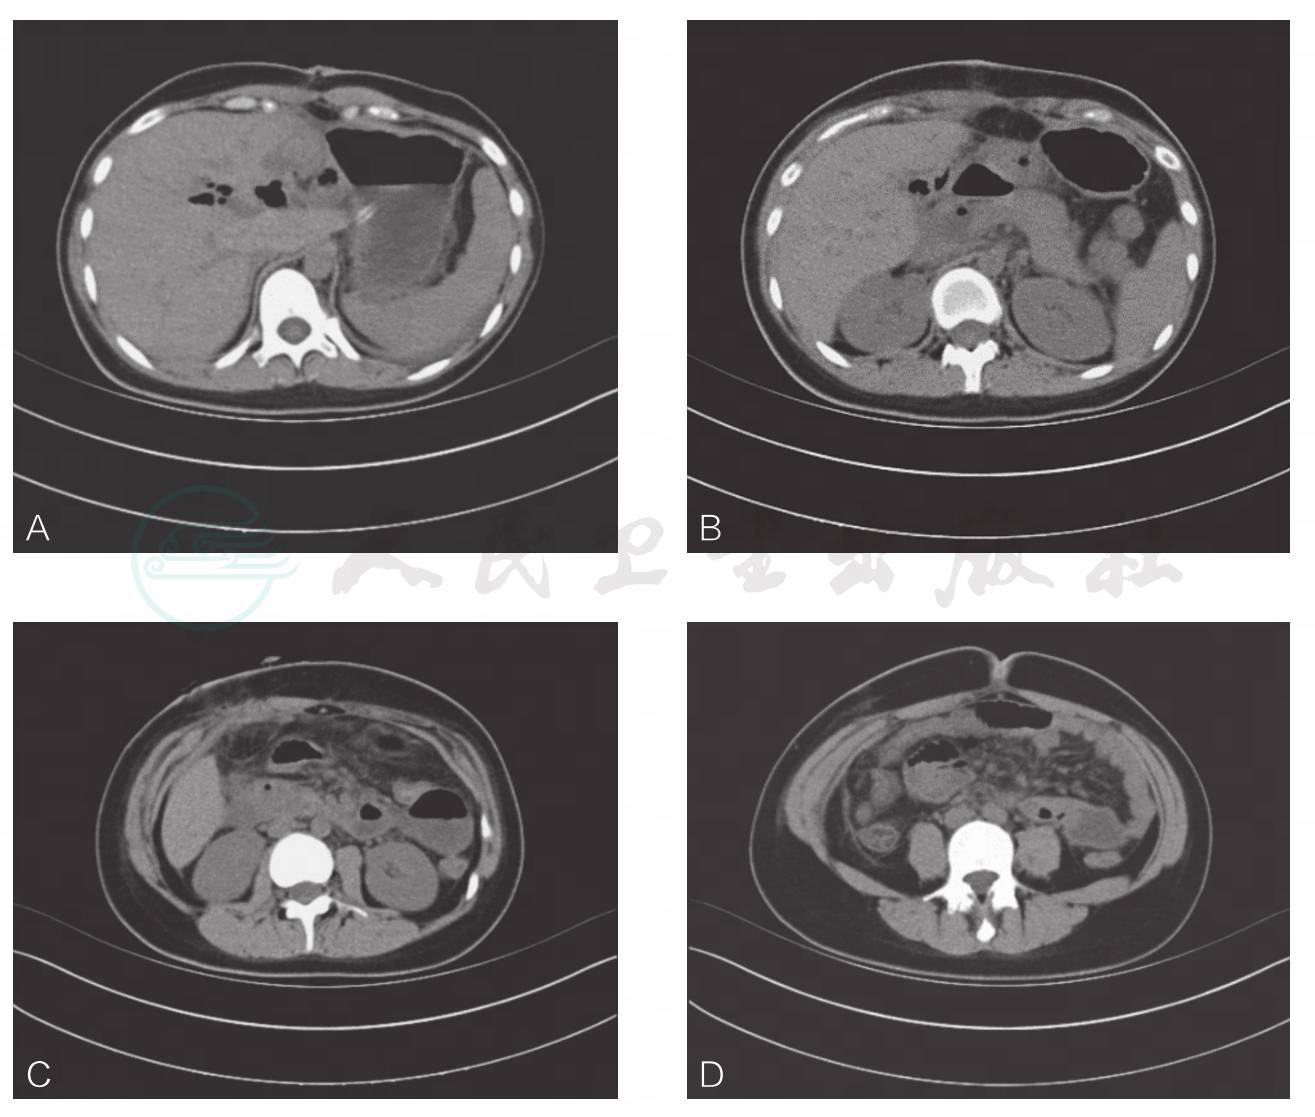

影像学检查:CT示:肝内胆管及胆总管多发结石,并肝内胆管扩张积气(图1)。MRCP示:肝内外胆管扩张,感染伴多发结石,胆总管囊肿伴感染、多发结石,胆囊显示不清(图2)。

图1 术前CT表现